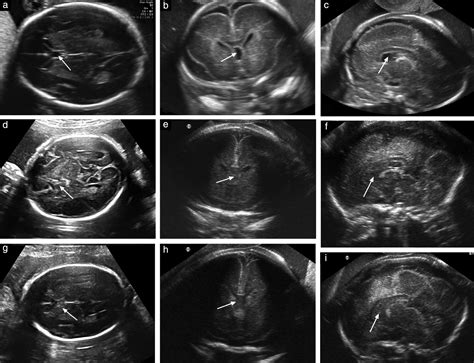

The Cavum Septi Pellucidi is a small, fluid-filled space located between the two leaflets of the septum pellucidum. The septum pellucidum is a thin, triangular, double membrane that separates the lateral ventricles of the brain. During normal fetal development, these two layers are separated by a space, which is the CSP.

The prevalence of a persistent CSP in the adult population is estimated to be between 1% and 3%, though some studies suggest it may be higher in certain demographics. Its appearance on imaging is distinct, typically appearing as a midline, fluid-filled structure that sits between the frontal horns of the lateral ventricles. Radiologists are well-trained to identify this feature and distinguish it from other, more concerning brain cysts or lesions.